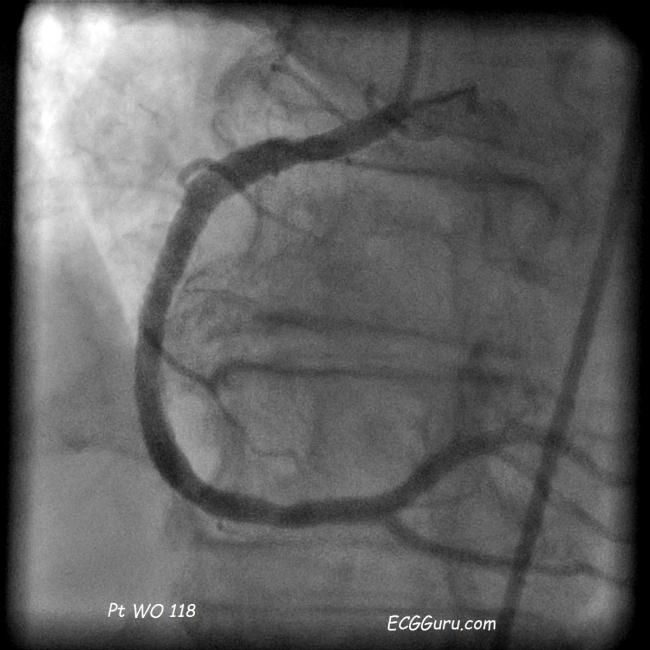

From www.ecgguru.com

Angioplasty ECG Guru Instructor Resources Jaw Pain After Angioplasty any chest discomfort or pain should go away when the balloon is deflated. This brochure provides essential information. “this is a common problem. But tell your healthcare provider right away if you. i had a stent fitted after being diagnosed with angina, but a week later i’m still having some chest pain. The pain may go away. Jaw Pain After Angioplasty.